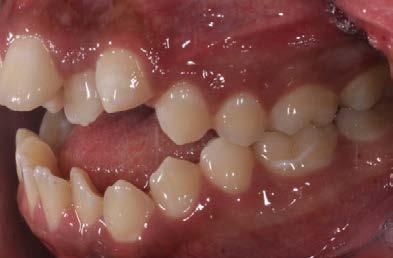

En los estudios intraorales de inicio en las fotografías se muestra en la de frente el diastema anterior, con la línea media dental superior e inferior no coincidentes, la mordida profun da anterior (Figura 2), en la lateral derecha clase l molar y canina bila teral (Figura 3), el apiñamiento leve superior e inferior y la forma de las arcadas.

hacia la derecha y la línea media dental inferior a la izquierda, con mordida abierta anterior, el canino superior derecho se encuentra fuera del arco ( Figura 3 ), en la oclusal superior los inci sivos laterales palatini zados y paladar ojival profundo, en la lateral derecha una relación molar clase II y relación canina no determinable (Figura 4), en la izquier da una relación molar clase I y relación canina no deter minada.